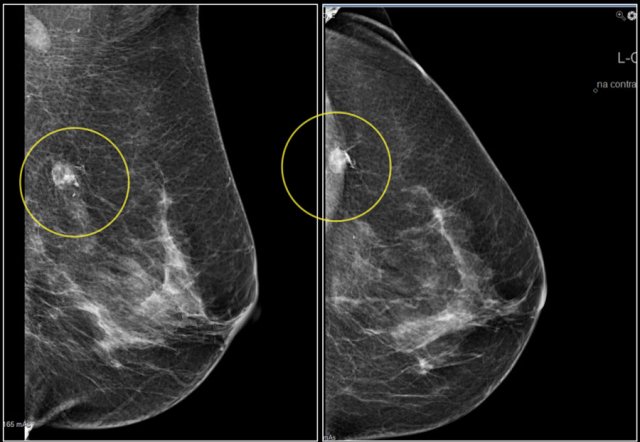

First study the images and describe the findings.

Then continue reading.

The findings are:

• Mass with irregular shape.

• Spiculated margin.

• High density.

• Ultrasound also shows irregular shape with indistinct margin.

This mass is categorized as BI-RADS 5.